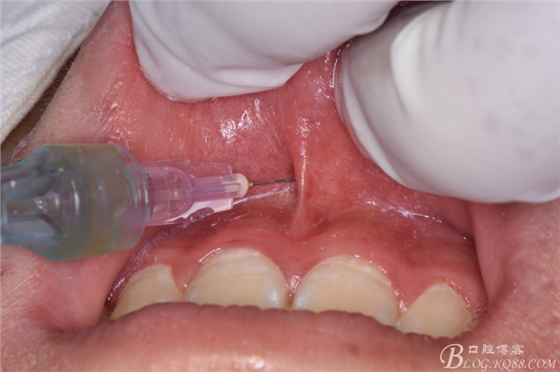

圖6.唇側(cè)局部無痛浸潤麻醉

圖7.腭側(cè)鼻腭孔麻醉